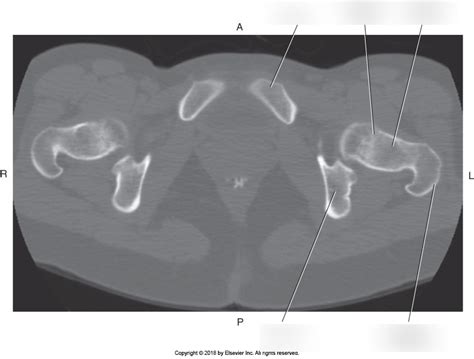

When we talk about the axial pelvis , we’re primarily referring to the pelvic girdle , which is made up of three main bones: the ilium , the ischium , and the pubis . These bones fuse together during adolescence to form the innominate bones , with each side of the pelvis having one. These innominate bones then join together at the front via the pubic symphysis and at the back with the sacrum , which is part of the vertebral column. This bony structure forms a ring that’s incredibly strong and stable, yet flexible enough to allow for movement. The ilium is the largest bone, forming the upper, flared part you can feel at your hips. It has a prominent crest, the iliac crest , which is a landmark for many medical procedures. Below the ilium, you have the ischium , which is the part you sit on – yep, that’s your “sitting bone”! Finally, the pubis forms the front and lower part of the pelvis, meeting its counterpart from the other side at the pubic symphysis. Together, these bones create the acetabulum , a deep socket that articulates with the head of the femur (thigh bone) to form the hip joint. This joint is a marvel of engineering, allowing for a wide range of motion while supporting your body weight. The intricate architecture of the axial pelvis, with its curves and articulations, is designed for maximum strength and efficient load transfer from the trunk to the lower extremities. It’s a testament to nature’s design, ensuring we can stand tall and move with grace. The way these bones are shaped and connected is key to its stability, preventing excessive movement that could lead to injury. The pelvis also plays a vital role in protecting internal organs, forming a protective basin for the bladder, reproductive organs, and lower parts of the digestive tract. So, while it’s a strong structural component, it’s also a vital protective cage for some of our most sensitive organs. The robustness of this bony framework is essential for countless activities, from the simple act of standing to the complex demands of athletic performance. Its deep sockets and strong ligaments ensure that the hip joints remain stable, even under significant stress.